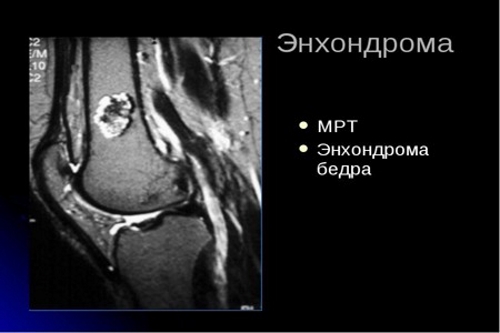

| Энхондромы | Доброкачественные опухоли хряща в костях кистей и стоп | Хирургическое удаление энхондром (при симптоматике), наблюдение |

- магнитно-резонансную томографию (МРТ);

На рентгеновских снимках видны асимметричные деформации, утолщения и укорочения костей, а также хрящевые новообразования. Для определения доброкачественного или злокачественного характера опухолей необходимо провести гистологический анализ образцов тканей. Важно отличить синдром Маффуччи от других заболеваний с похожими симптомами.